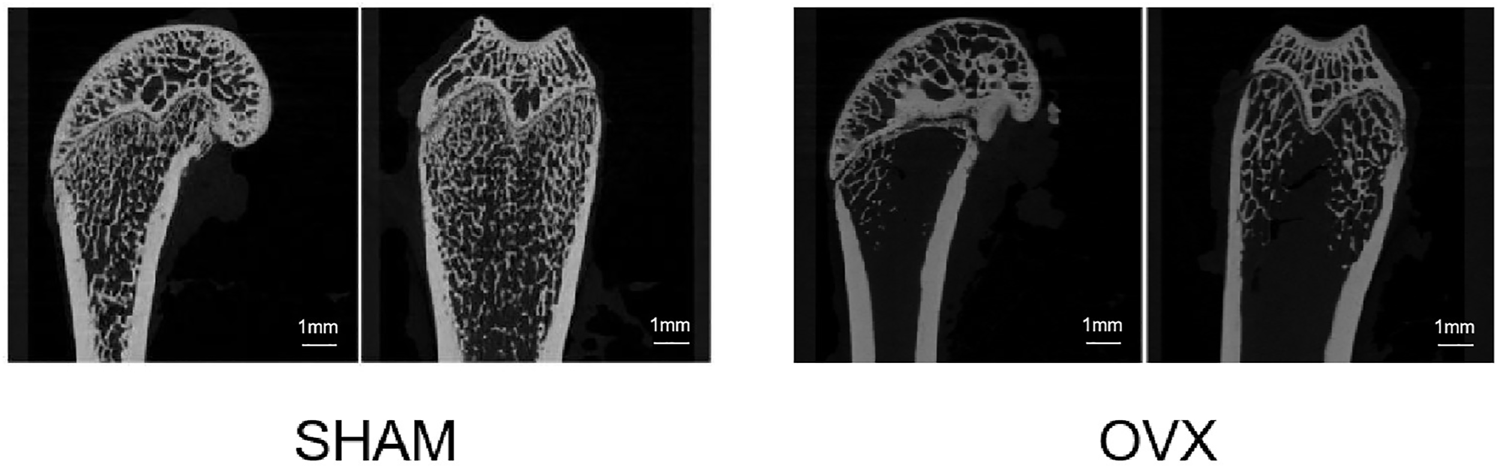

Scanning Results of OP Mouse Model

Figure 7 shows the micro-CT images of the femur in the sham and OVX groups. Bone density was significantly lower in the OVX group than in the sham group, indicating that the animal model of OP was successfully constructed.

FIGURE 7

Micro-CT scan section of rat femur. Compared to the sham operation (SHAM) group, the bilateral ovariectomized (OVX) group had reduced bone trabecular density and successful osteoporosis modeling.